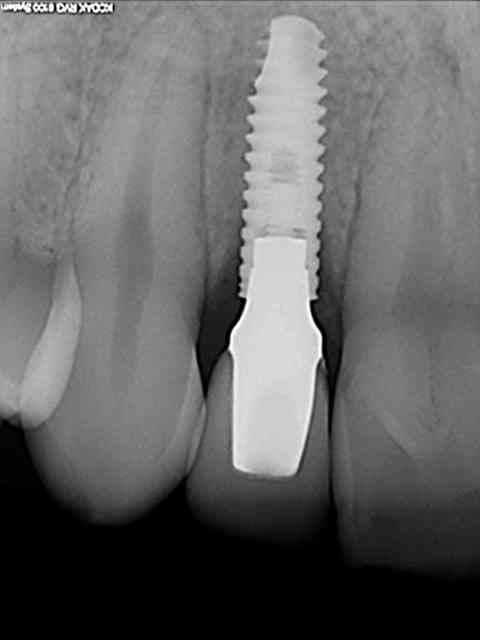

tes implants 12 et 13 n'ont pas le même niveau d'enfouissement, tu n'as pas peur d'une lyse osseuse de 13 pour venir au niveau du col de 12 ?

01/09/2010 à 16h54

-1 ou 2 mois plus tard ( je sais plus)

- empreinte avec transfert pop in

- pilier zircone esthétique Axiom

- prothèse et pilier

- pilier zircone en place

- couronne en place (petite compression gingivale)

fin du traitement